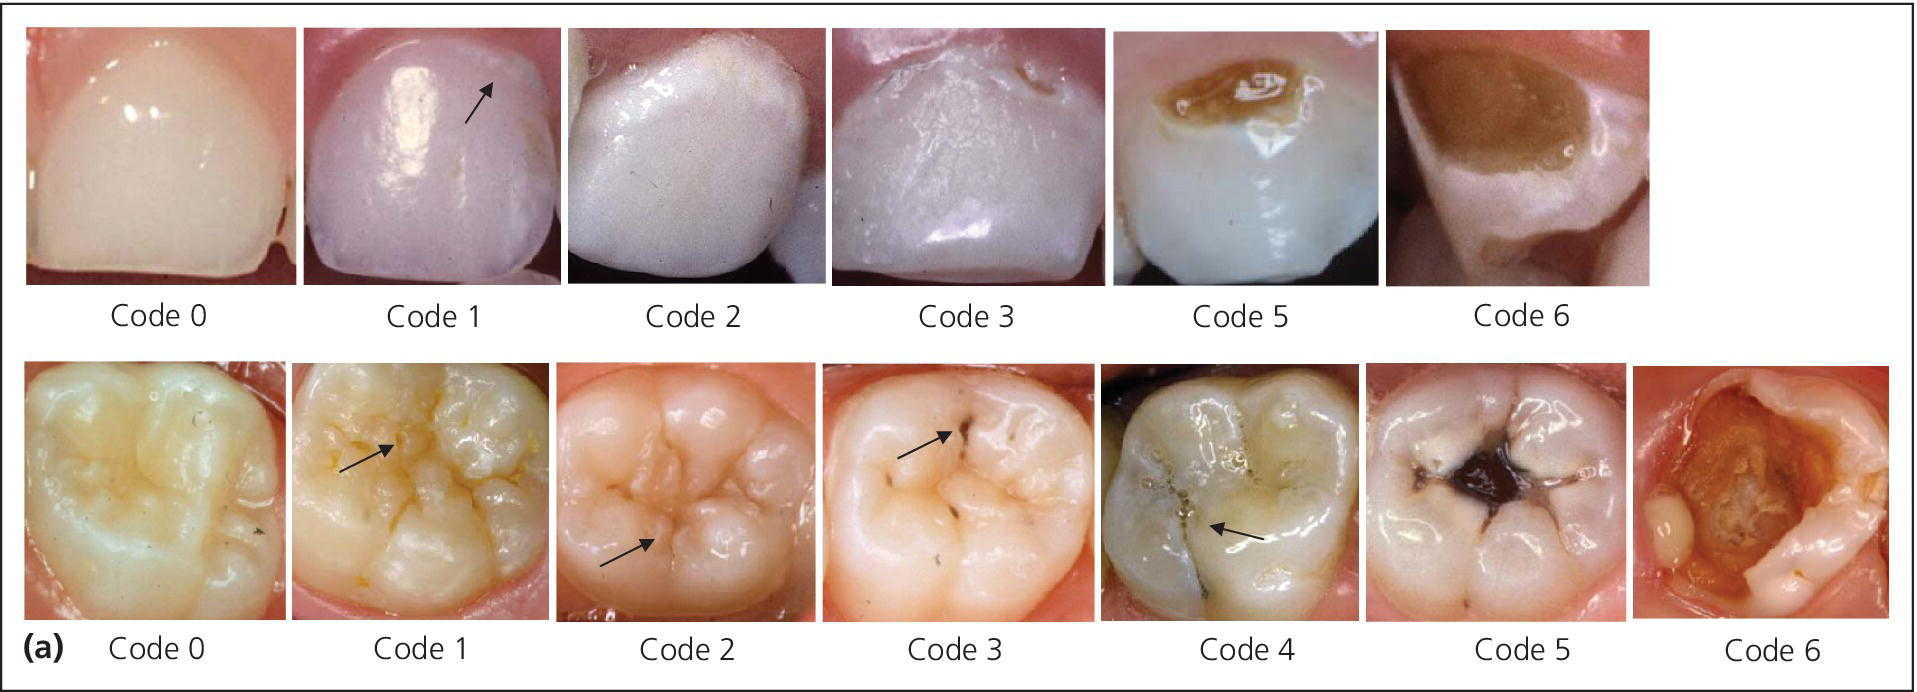

Diagnosis And Management Of Dental Caries - Pediatric Dentistry - A

doctorlib.info

doctorlib.info

caries pediatric dental diagnosis dentistry clinical teeth cavities approach treatment lesions after management discoloration properties fluoride fissures based 3ed releasing

12: Diagnosis And Management Of Dental Caries | Pocket Dentistry

pocketdentistry.com

pocketdentistry.com

caries dental dentistry clinical diagnosis icdas management pediatric surfaces tooth lesion smooth teeth occlusal enamel criteria grading pit severity fissure